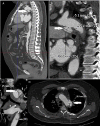

We present a case of a 67-year-old man who was an active smoker, with a clinical history of ischaemic cardiopathy, hypertension, who presented to the emergency room with hoarseness of voice of 2 weeks duration. No other neurological or cardiorespiratory symptoms were found. Physical examination revealed an aortic regurgitation murmur with radial pulse difference between the upper limbs and femoral pulse difference on lower limbs. Laryngoscopy examination revealed a left vocal cord paralysis in the paramedian position, without signs of malignancy. Thoracoabdominal CT angiography was performed to rule out an aortic dissection. CT revealed a dissection in the descending thoracic aortic arch and abdominal aorta. Cardiovascular surgery was consulted and decided to place endoprosthesis at the thoracic and abdominal aortic area. Hoarseness eventually resolved during the following weeks. Ortner's syndrome is described as hoarseness of voice caused by compression of the left recurrent laryngeal nerve of cardiovascular origin.